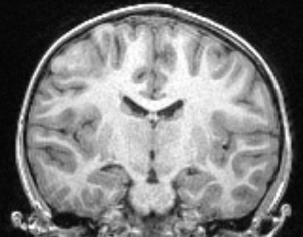

Au décours d’une crise d’épilepsie, une patiente âgée de 11 ans, sans antécédent, est hospitalisée

ÉEG : anomalies focales sous F4 FC2, en regard de l’anomalie frontale latérale étendue retrouvée sur l’IRM cérébrale